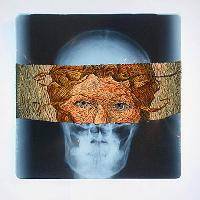

Изучение проблемы низкого качества рентгенограмм на Вашем оборудовании.

Мобильный рентгенаппарат + оцифровщик. Получение рентгеновского изображения на экране ноутбука. Вариант за 1,4 миллиона рублей под ключ.

Мобильный рентгенаппарат с печатью рентгенограмм на рентгеновской пленке. Цена 700000 рублей.